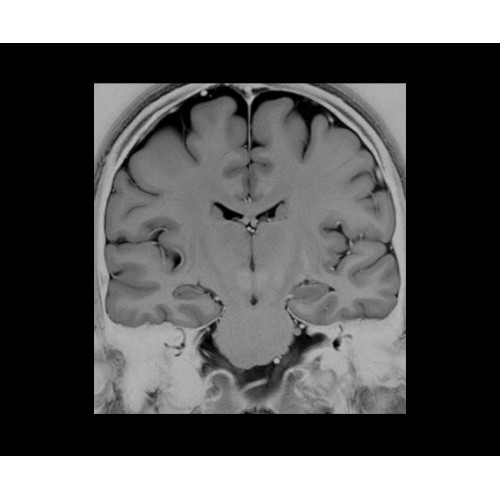

• NeuroWorks — универсальное решение для визуализации анатомии головного мозга, позвоночника, сосудов и периферических нервов с четкой дифференциацией тканей.